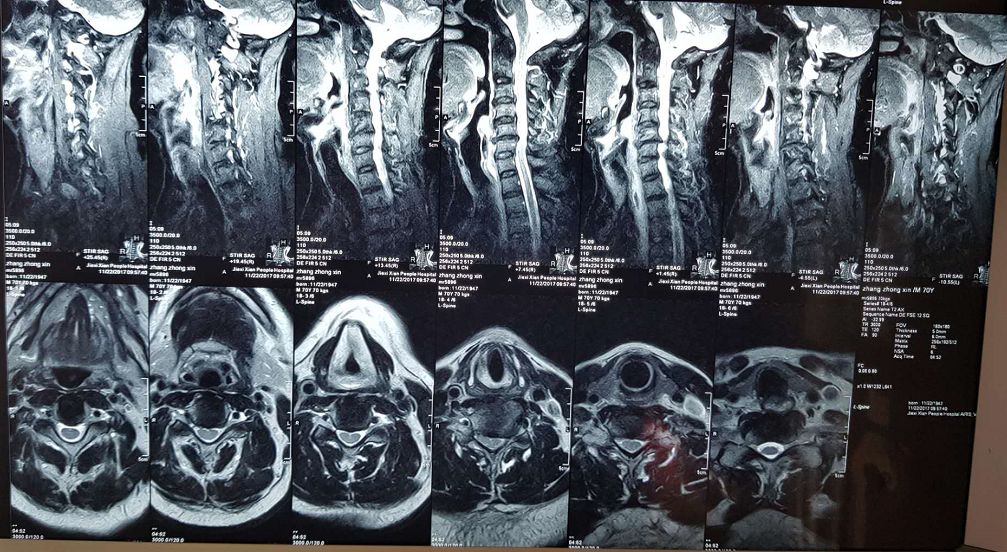

2018年5月26日,揭西县人民医院外一区(骨外科)曾石远副教授在中山大学孙逸仙纪念医院李春海教授合作指导下共同完成了揭西首例“脊髓型颈椎病手术”(经前路颈间盘切除减压椎间植骨融合内固定术),此例脊髓型颈椎病的患者出现反复腰痛并双下肢步行不稳、脚踩棉花感的症状(有近10年病史),术后患者症状体征快速得到明显的改善。